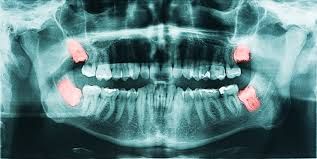

Your dentist may refer you to an oral and maxillofacial surgeon for wisdom tooth evaluation in your early teenage years with the goal of preventing problems such as dental crowding, pain, infection, and cyst development before these issues start.

With an oral examination and imaging of the jaw bones, your oral and maxillofacial surgeon will evaluate the position of the wisdom teeth and make recommendations for surgical removal if indicated.